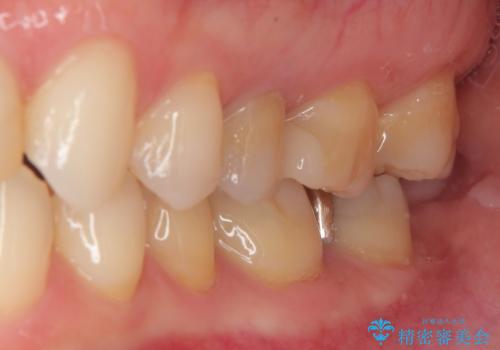

- 銀歯がとれたのでやり替えたいとのことで来院された患者様です。来院時特に症状もなく金属の詰め物(メタルインレー)がとれたのでセラミックの詰め物(セラミックインレー)にやり替えていくことになりました。また患者様のご希望によりひとつ後ろの歯の金属の詰め物(メタルインレー)のやり替えも同時に治療していくことになりました。

拡大鏡視野下で、金属の詰め物(メタルインレー)、保険のプラスチック、虫歯の除去を行い、セラミックインレーに適した形に整えました。

歯と歯茎の間に圧排糸と言われる糸を入れてシリコーン印象材にて精密な型どりをしました。